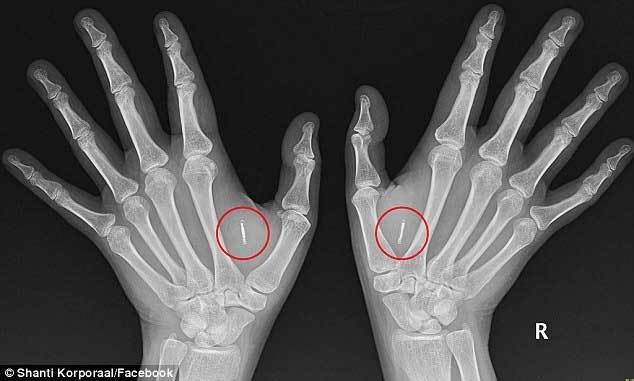

Shanti Korporaal, ở Sydney (Australia), hiện là tâm điểm của hiện tượng này. Cô đã cấy hai vi mạch vào hai tay và hiện giờ dùng nó như thể mình có năng lực siêu nhân. Shani có thể vào chỗ làm hoặc vào xe ô tô mà không cần mang thẻ hay khóa.

Theo Shanti, vi mạch được cấy gần như không thể phát hiện vì nó chỉ bé như một hạt gạo. Vi mạch này có thể được dùng như một tấm danh thiếp và chuyển thông tin liên lạc sang điện thoại di động và nắm giữ nhiều thông tin phức tạp.